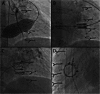

There is a growing appreciation for the adverse long-term impact of right-sided valvular dysfunction in patients with congenital heart disease. Although right-sided valvular stenosis and/or regurgitation is often better tolerated than left-sided valvular dysfunction in the short and intermediate term, the long-term consequences are numerous and include, but are not limited to, arrhythmias, heart failure, and multi-organ dysfunction. Surgical right-sided valve interventions have been performed for many decades, but the comorbidities associated with multiple surgeries are a concern. Transcatheter right-sided valve replacement is safe and effective and is being performed at an increasing number of centers around the world. It offers an alternative to traditional surgical techniques and may potentially alter the decision making process whereby valvular replacement is performed prior to the development of long-term sequelae of right-sided valvular dysfunction.